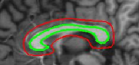

Refer to captionRefer to captionRefer to captionRefer to captionRefer to captionRefer to captionRefer to captionRefer to captionRefer to captionRefer to captionRefer to captionRefer to caption\begin{array}[]{cc}\includegraphics[width=112.0187pt]{lv-2-init.pdf}&\includegraphics[width=112.0187pt]{lv-2.pdf}\\ \includegraphics[width=112.0187pt]{lv-3-init.pdf}&\includegraphics[width=112.0187pt]{lv-3.pdf}\\ \includegraphics[width=112.0187pt]{lv-1-init.pdf}&\includegraphics[width=112.0187pt]{lv-1.pdf}\\ \end{array}

Figure 15: Segmentation of left ventricle wall of the heart in an MR image taken from [42]. Left column shows initialization and right column shows converged result.

We next develop templates for objects with hole(s) in their structure. These templates are called ring templates. Figures 15 and 16 show examples of ring templates. The area enclosed between the red contours act as region 1subscript1\Re_{1} and the area between the green contours is region 0subscript0\Re_{0}. Figure 17 shows the construction of the ring contours. The two seemingly unconnected contours are actually one connected contour. Hence, partial derivative calculations in equation (26) are still valid.

In Figure 15, the ring template has been used for segmenting the left ventricular (LV) wall of heart in cardiac MR images. Another example is shown in Figure 16. The template used in both examples has a greater thickness in the inner ring-shaped annular region than the outer annular region. This was done to facilitate obtaining the desired object’s structural information by means of the contrast (for example, between the endocardium and the LV wall) that a good initialization can offer. Hence, while designing a template, we can incorporate prior knowledge of the object and its surroundings.